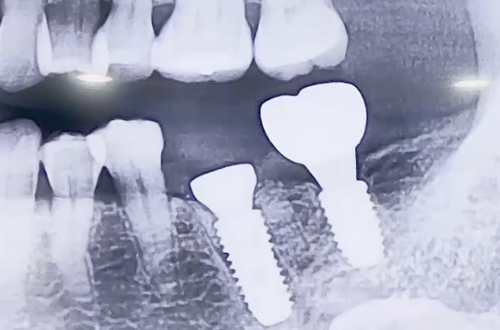

AFTER

발치 즉시 임플란트를 식립하고 빈 공간을 뼈이식으로 채운 뒤,

임플란트 기간동안 해당 부분을 보호할 수 있도록 힐링 어버트먼트를 사용했습니다.

임플란트가 굳기까지 4개월을 기다린 후 보철을 연결하여 치료를 마무리하였습니다.